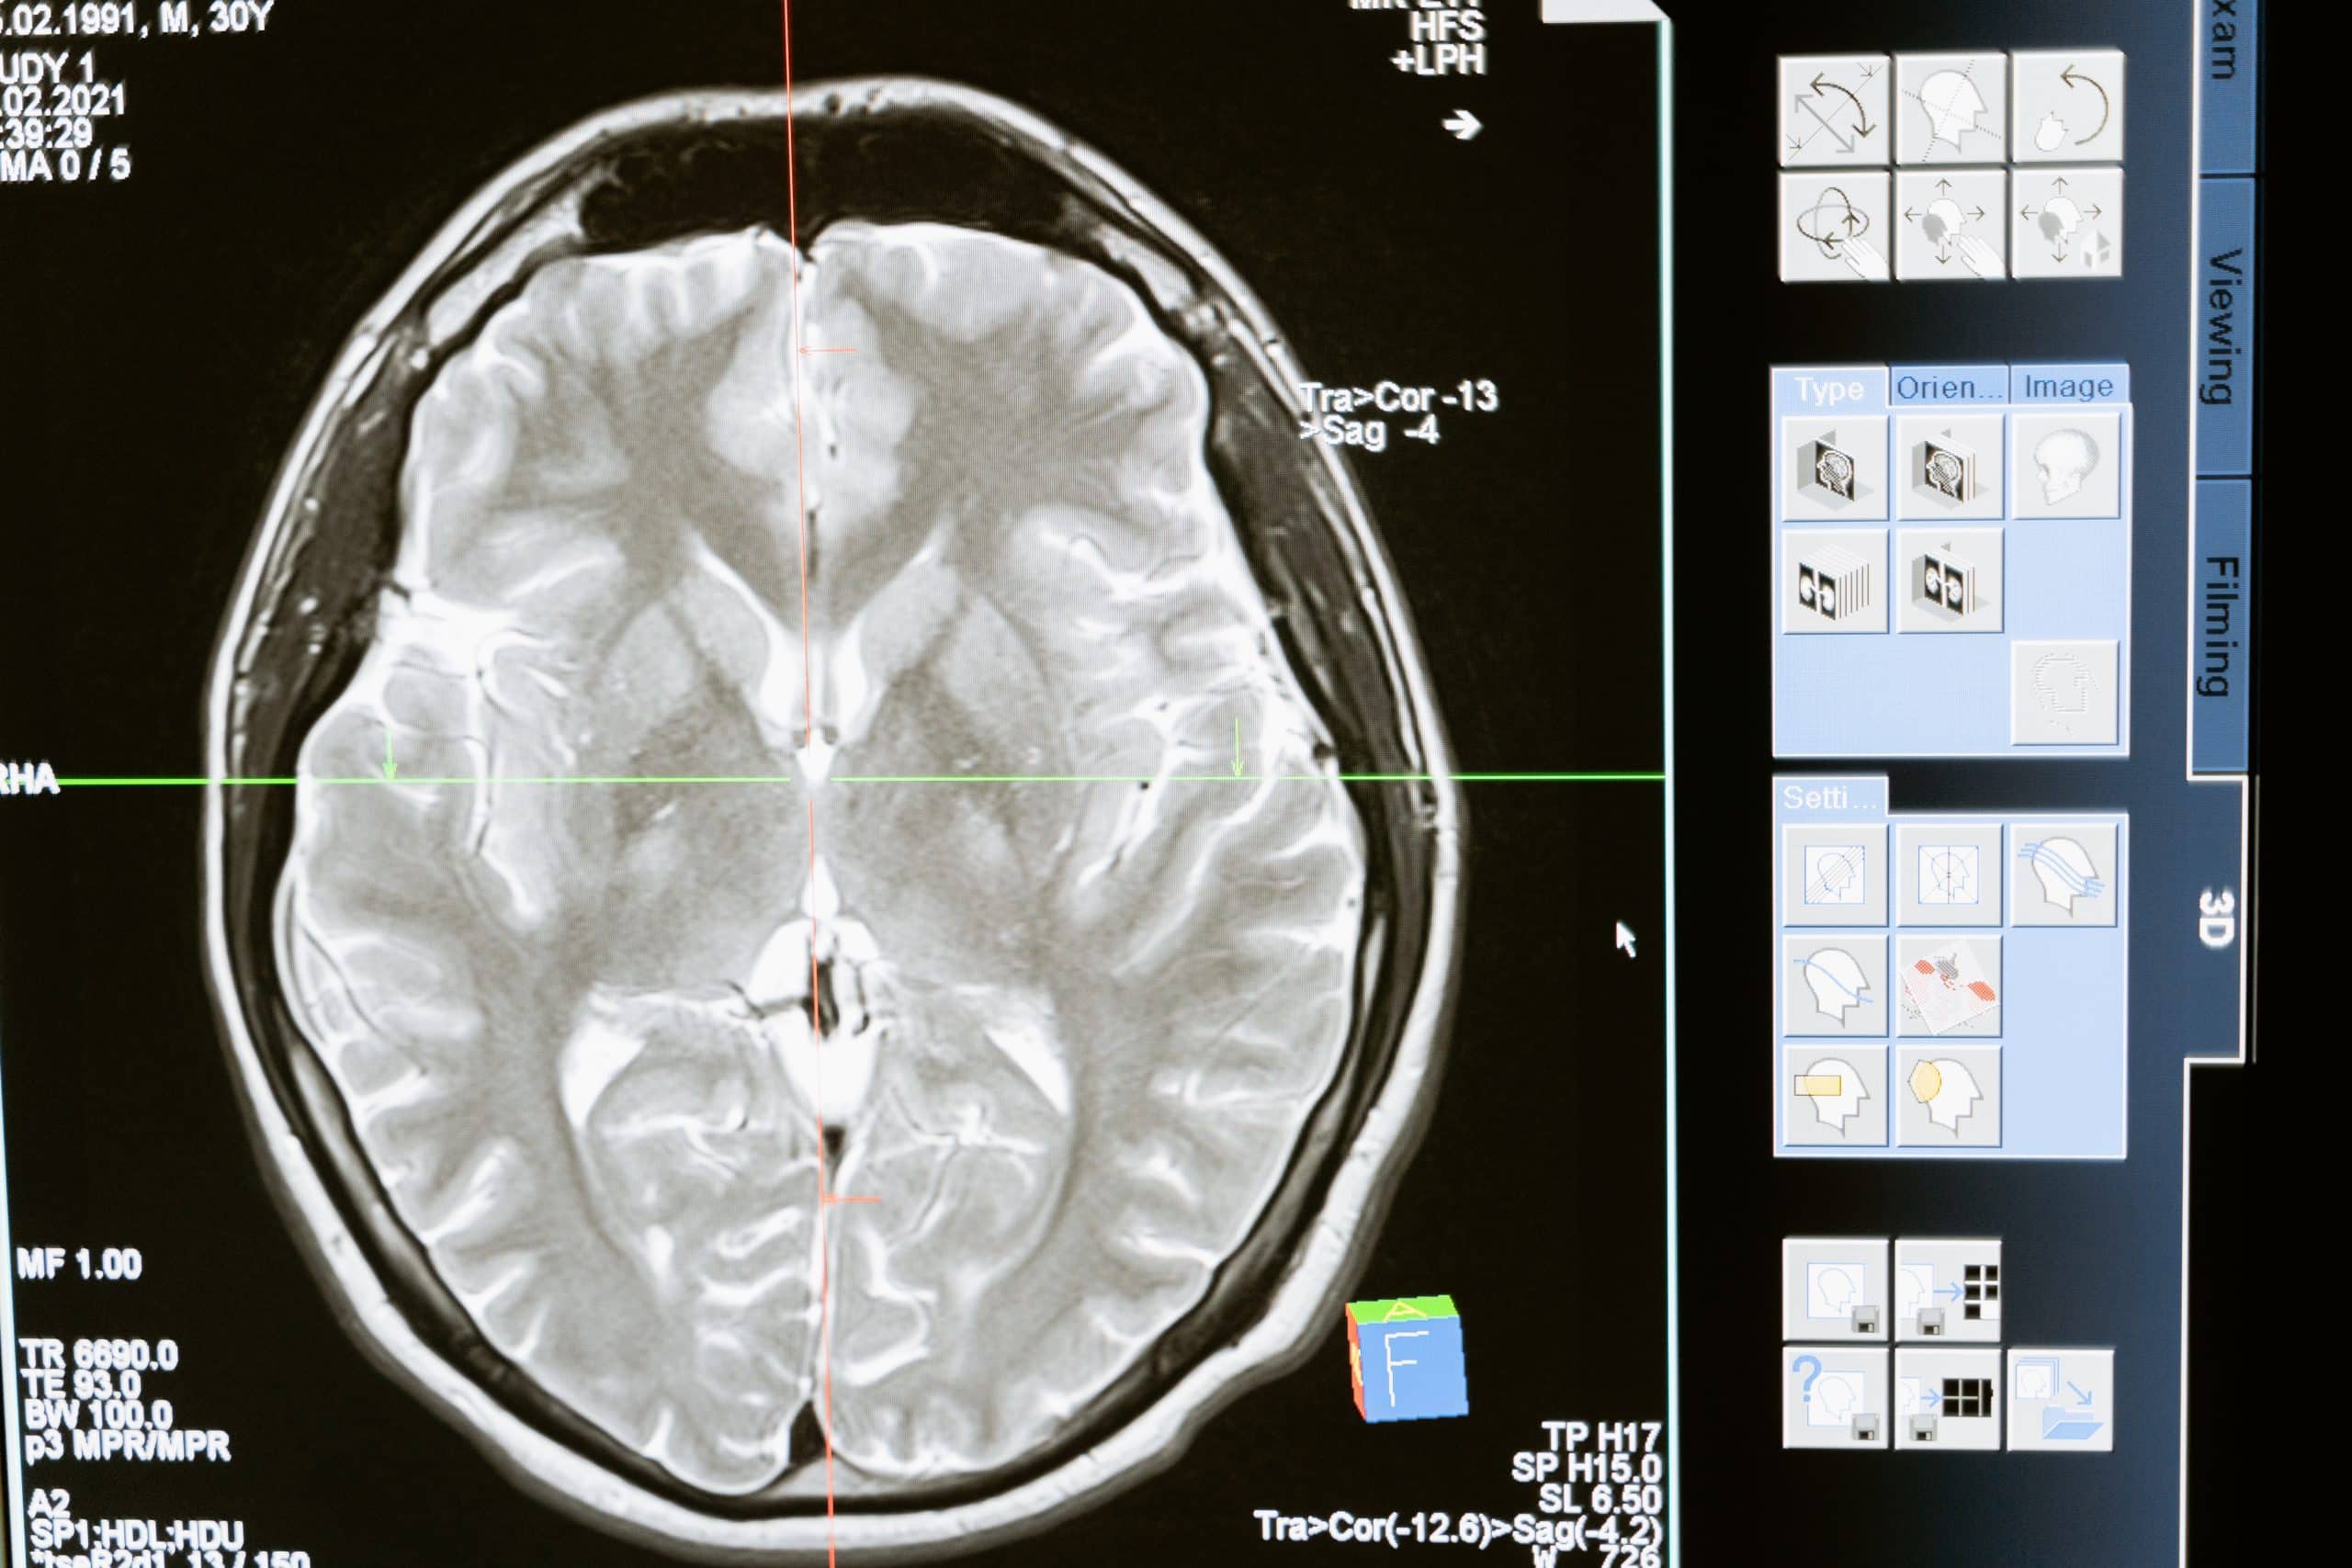

Brain injuries can be caused by any incident that causes an impact to the head, from car accidents to falls. Any time the brain is injured, there is potential for long-term damage. The severity of the injury will depend on the extent and location of the damage, as well as how quickly emergency treatment is received.

A traumatic brain injury (TBI) occurs when an outside force disrupts the normal function of the brain. For example, when the head suddenly and forcefully hits an object, or when an object penetrates the skull and enters brain tissue.

According to the Centers for Disease Control and Prevention (CDC), TBI is a leading cause of death and disability in the U.S. TBIs can range from mild, which may only cause temporary disruptions in brain function, to severe, which can result in long-term neurological problems or death. In our firm, an attorney for person with traumatic brain injury can provide vital legal support, especially when dealing with severe TBIs that may require hospitalization and extensive, ongoing care. Severe TBIs may require hospitalization and extensive, ongoing care.

Treatment for TBIs depends on the severity of the injury and may include surgical intervention, medication, physical therapy, and rehabilitation. Depending on the cause of your injury, brain injuries lawyers may be able to help you get the compensation you deserve after experiencing a TBI.